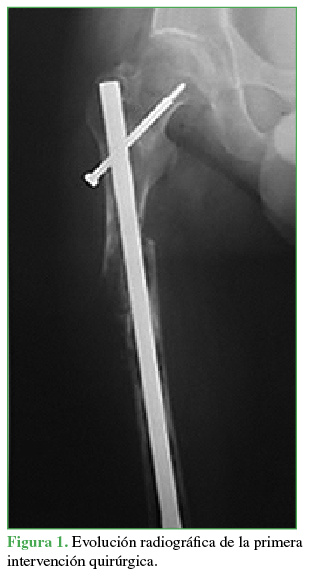

La evolución posoperatoria a corto plazo fue mala, con osteosíntesis fallida asociada a imágenes heterogéneas y líticas difusas a nivel diafisario (Figura 1).

Figura 1

Evolución radiográfica de la primera intervención quirúrgica.